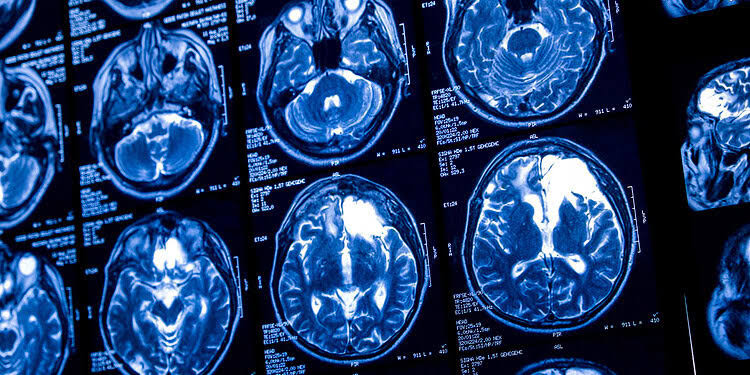

Even light drinking combined with aging is linked to reduced brain blood flow and thinner tissue

A recent study published in the journal Alcohol provides evidence that even low-level drinking may have negative consequences for brain health over a...